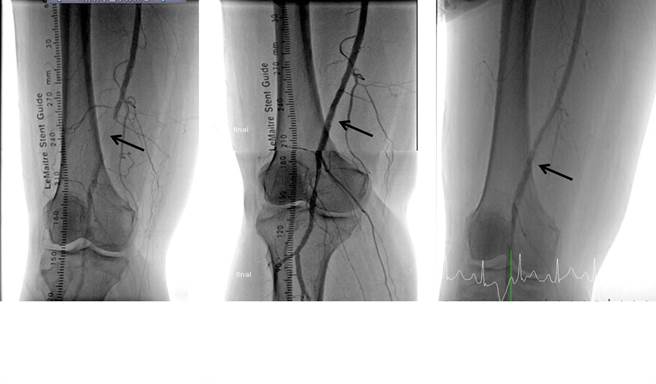

61岁朱姓男子术前及术后影像。(丰原医院提供)

另名57岁叶姓女子患有第2型糖尿病,规则服药及胰岛素控制,因右脚第三脚趾伤口1个多月未癒合,伴有双下肢水肿,右脚红肿及疼痛,由外科转介心臟科张伟俊医师门诊,经动脉分段血流及压力测定(ABI)检查,结果显示右脚有严重的周边动脉阻塞及左脚有中度的周边动脉阻塞。下肢电脑断层血管摄影显示右侧股浅动脉远端阻塞,2021年5月做经皮气球血管扩张术,并使用涂药气球,放置金属支架,持续追踪1年都没有再发生阻塞情形。